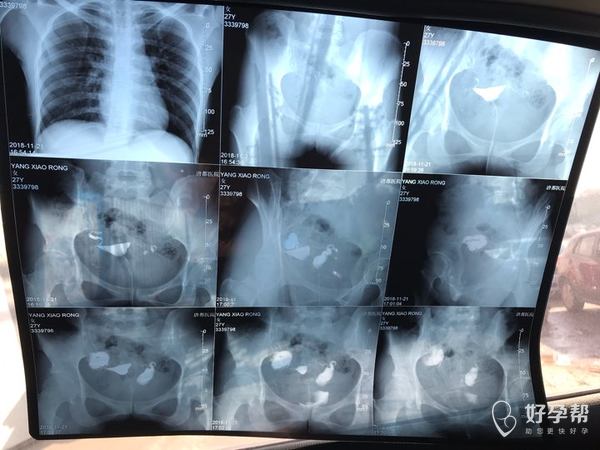

麻烦各位教授给我看看输卵管造影片子,谢谢了🙏

您好,输卵管堵塞,建议切除输卵管做试管,保守保守治疗没有多大意义,觉着我的回复对您有帮助记着帮忙点击采纳,谢谢!